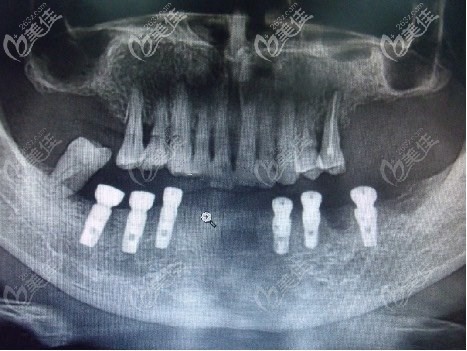

醫(yī)生為了看到準確的牙槽骨、牙齒情況,建議先拍CT看看。

從上圖可以看出老人下牙壞死并缺失多顆,殘存的也都松動了,根據老人牙槽骨條件,醫(yī)生給老人的建議是做半口種植牙修復,這個技術院內做的比較成熟,成功率也比較高,老人可能對這個也不了解,說是要考慮考慮。

醫(yī)生把CT片拿出來,把種植方案分析給他聽,兒子覺得父親也年級大了,平常愛吃豆面湯圓都吃不好,覺得是得給父親做口好牙。